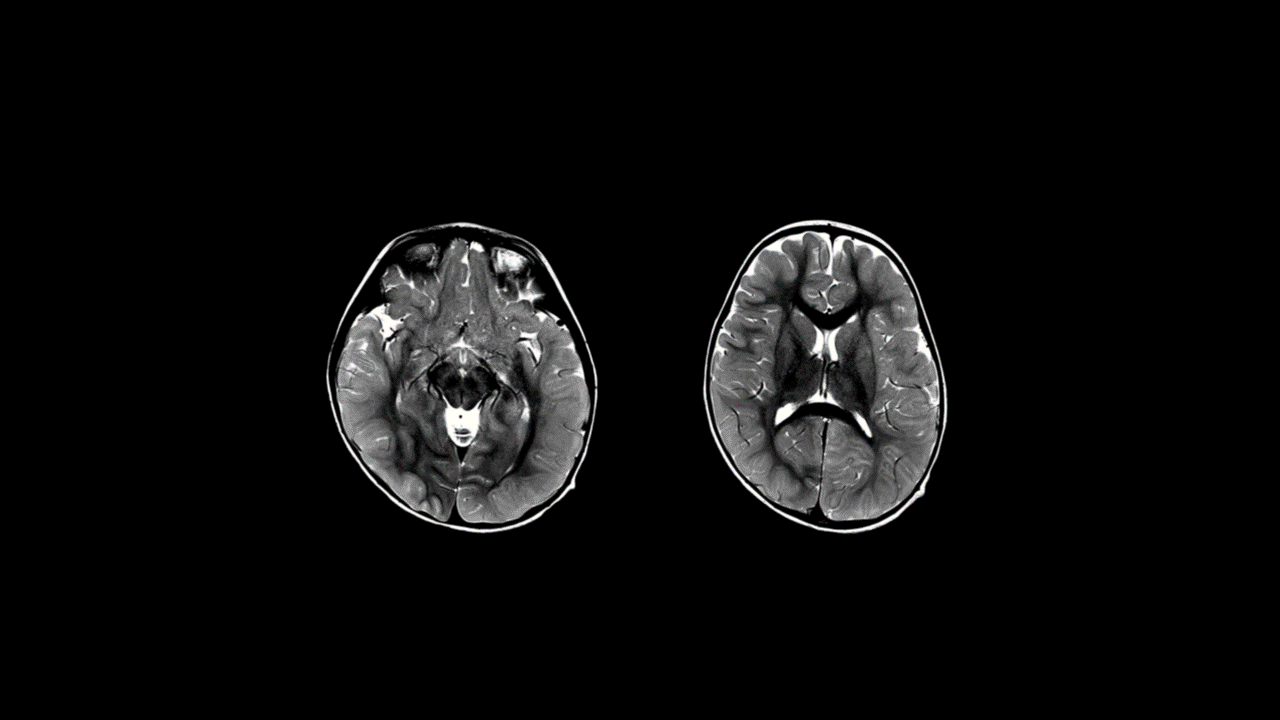

Symmetric areas of Restricted Diffusion in the bilateral temporal and parieto-occipital subcortical and periventricular white matter and in the bilateral frontal subcortical white matter. The white matter depicts a “bright tree appearance” which represents high-signal intensity on DWI B1000 in the subcortical white matter, akin to tree branches.

Areas of Restricted Diffusion are also seen in the leftthalamus, caudate nuclei bilaterally, dorsal pons, inferior cerebellar cortex in the paramedian location and in the superior vermis.

Subtle thickening of the cortex in the bilateral parieto-occipital regions with mild blurring of gray-white matter interface in these regions.

Imaging features suggest diffuse type Acute Leukoencephalopathy with Restricted Diffusion - ALERD